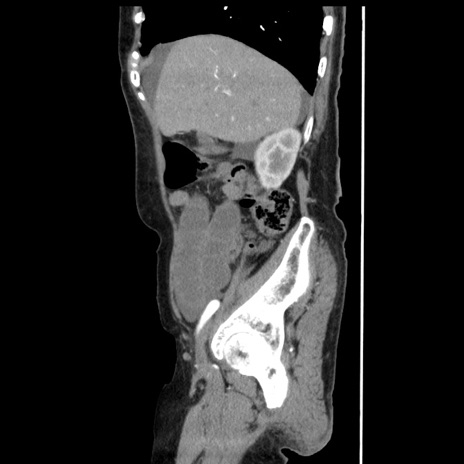

冠状断像

【症例】80歳代女性

【主訴】腹痛

【現病歴】8時間前から腹痛あり来院。

【既往歴】糖尿病、脂質異常症、子宮体癌にて子宮全摘術

【身体所見】意識清明・会話良好だが腹痛で苦悶様、全腹部にわたって反跳痛と圧痛あり

【データ】WBC 13600、CRP 0.14、LDH 224、CK 90